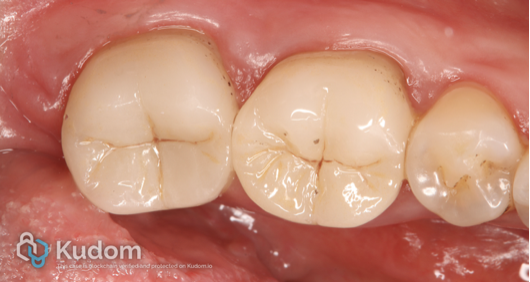

Fig. 1

The pre-operative intraoral photograph shows two adjacent mandibular molars restored with extensive amalgam restorations. Both restorations appear old and defective, with evident marginal breakdown and loss of anatomical contour. The proximal margins between the two molars are compromised, with food and plaque accumulation and recurrent caries. Discoloration around the restoration margins and areas of exposed tooth structure indicate microleakage and deterioration of the remaining enamel and dentin. The surrounding gingival tissues appear mildly inflamed, likely due to plaque retention associated with the defective restorations. These clinical findings, in conjunction with the radiographic assessment, confirm the failure of the existing amalgam restorations and the need for comprehensive restorative management, including endodontic treatment for the affected tooth followed by definitive coronal restoration.